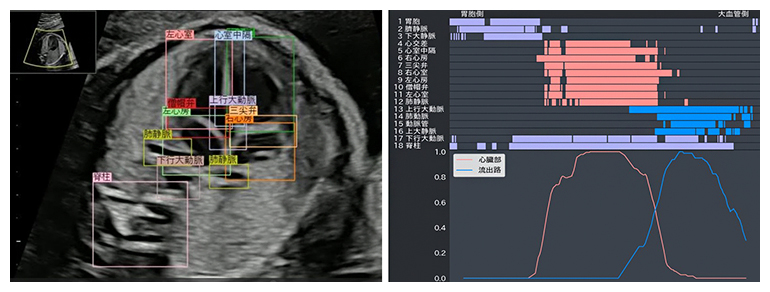

今回、共同研究グループが開発したAIシステムでは、胎児心臓超音波スクリーニング動画において確認すべき心臓血管構造の18部位を対象として物体検知技術[2]を適用し、正常構造として検出された部位を色付き枠で提示しました。次に、その部位検出情報を2次元データに変換し、縦軸に対象部位、横軸に検査時間経過を示し、各部位の検出結果を時系列で一覧表示するバーコードを生成しました。さらに、検査者が把握しやすいように心臓部[3]および流出路[3]を対象とした部位検出結果を検出率グラフで提示しました(図1)。正常胎児では、超音波プローブのスイープ走査に合致して、各診断部位を順番に検出できます。一方で、正常胎児が示すバーコードや検出率グラフから逸脱していた症例については、異常を疑う所見ありとして検査者に注意喚起を行います(異常検知[4])注6)。

図1 バーコードと検出率グラフ

左図:胎児心臓超音波スクリーニング動画上で検出された部位を色付き枠で囲む。右上図:縦軸に対象となる18部位、横軸に検査時間経過を示し、各部位の検出結果を時系列でバーコード表示。右下図:心臓部および流出路を対象とした部位検出結果を検出率グラフで示す。AIシステムのバーコードおよび検出率グラフにおいて、心臓部:9部位(心交差、心室中隔、右心房、三尖弁、右心室、左心房、僧帽弁、左心室、肺静脈)を赤色、流出路:4部位(上行大動脈、肺動脈、動脈管、上大静脈)を青色で示した。

このたび薬事承認を取得した胎児心臓超音波スクリーニング支援システムはクラウド環境で提供されます。超音波画像診断装置からからキャプチャーボックスを経由してビデオ信号で映像を取得し、クラウドサーバ上で解析後、解析結果を汎用コンピュータ画面に表示します。解析結果はクラウドサーバ上に保存することも可能です(図2)。なお、AIシステムの主な機能は検査者の超音波診断への補助であるため、AIシステムが提供する情報のみで診断せず、最終的な診断は専門知識を有する医師が行います。

図2 AIシステム構成と利用イメージ

胎児の全身を観察している間(20~30分)に、胎児心臓スイープ動画(10秒)を取得する。スイッチを操作すると、自動的に取得映像がクラウドサーバへ送信され、クラウドサーバ上でAI解析後、汎用コンピュータ画面に解析結果が表示される。検査者は同一検査中に解析結果を確認することができる。